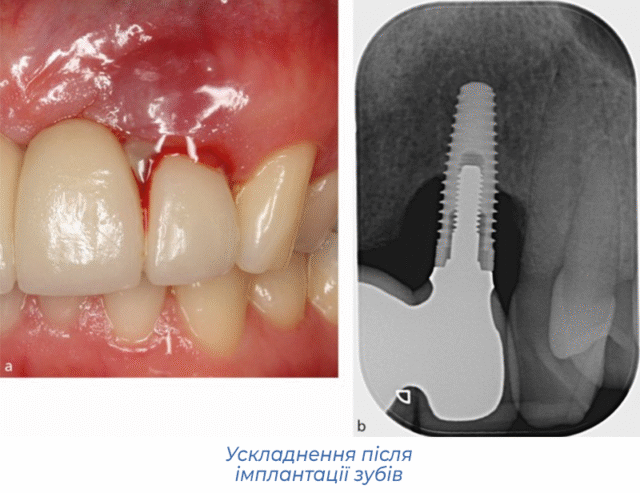

Діагностика: КТ, рентген, огляд

Для проведення успішного лікування стоматологу необхідно зрозуміти, чому не прижився імплантат. Лікар починає прийом з уточнення скарг та огляду ротової порожнини, під час якого оцінює місцеві ознаки запалення.

Далі він направляє пацієнта на рентгенографію зубів або КТ. Отримані знімки показують стан тканин навколо імплантату зуба та дозволяють поставити правильний діагноз.